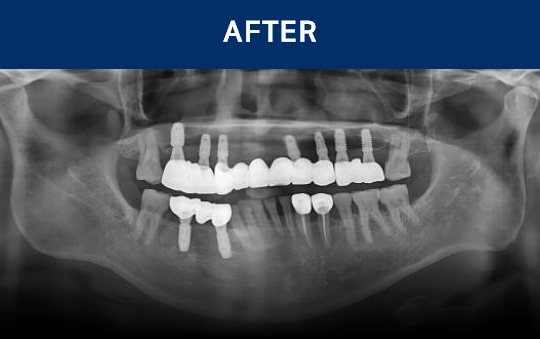

清晰可见的成果,

就是新吉种植牙

科值得信赖的证明.

通过种植牙, 让您无忧进食, 自在微笑, 重拾生活的舒适感